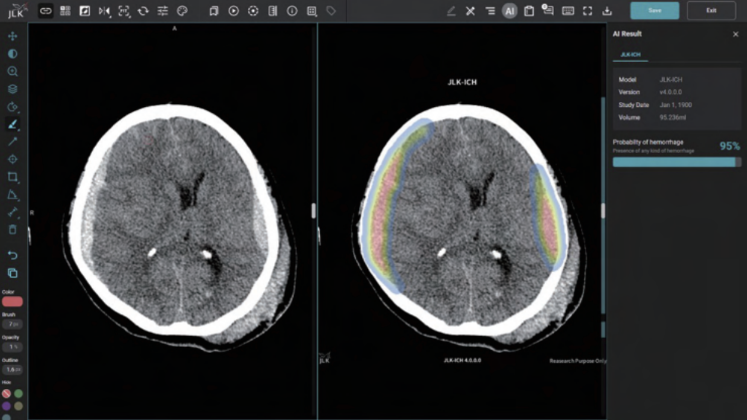

회사에 따르면 JLK-ICH는 제이엘케이가 주력하고 있는 뇌졸중 AI 솔루션으로 환자의 뇌 CT 영상을 분석해 뇌출혈 영역을 검출하는 AI 솔루션이다. 통상 뇌졸중 의심환자가 응급실에 도착하면 가장 먼저 뇌 CT를 촬영해 뇌출혈 여부를 확인한다. JLK-ICH가 이 과정에서 빈번히 쓰일 것으로 예측된다.

혈관이 막히는 뇌경색 대비 중증도가 높은 뇌출혈은 출혈 크기 증가 우려와 재출혈 위험으로 치료까지 걸리는 시간을 단축하는 것이 환자 예후개선에 필수적이다. JLK-ICH는 임상연구를 통해 발생 특징이 다른 5가지 뇌출혈 유형에 대해 편차 없는 높은 검출 성능을 입증한 만큼 골든타임 확보에 큰 역할을 할 것으로 기대된다.